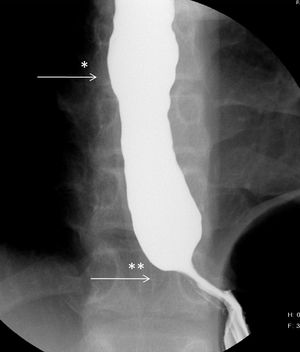

Proximal part of esophagus is dilated and distal part is closed

Achlasia cardia

achalasia cardia is caused by loss of inhibitory ganglion in the myenteric plexus of the esophagus.is a progressive motor disorder.